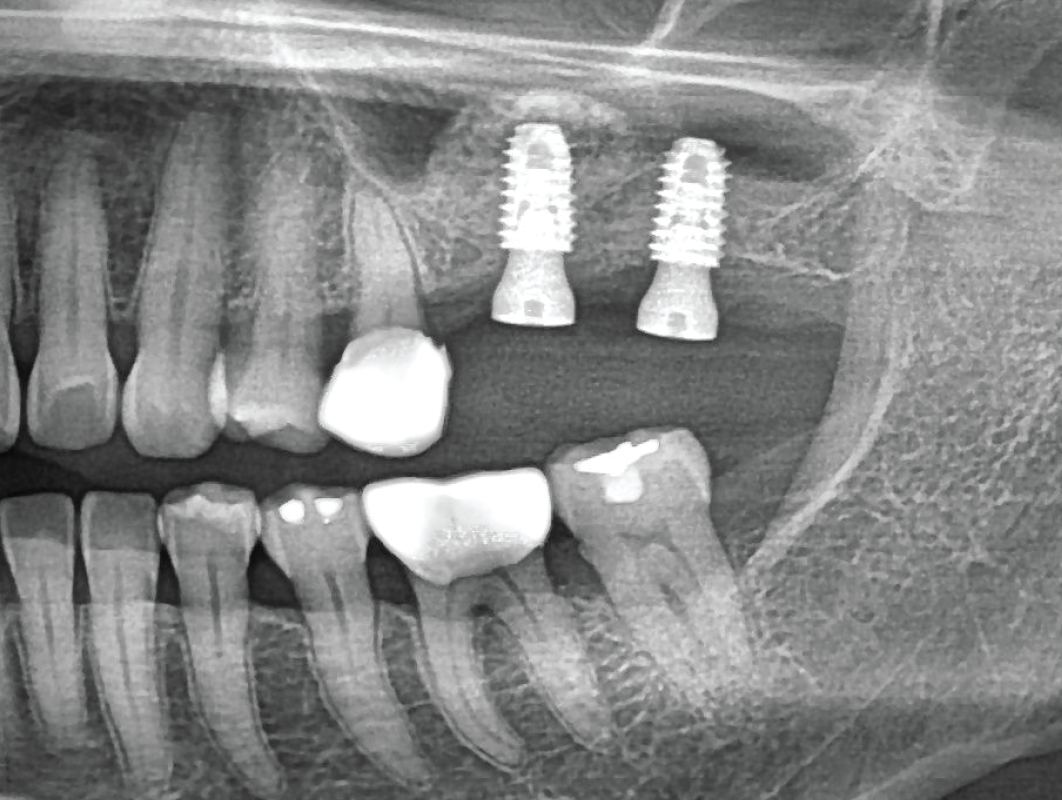

PRE-RACE DIAGNOSTICS – PREOPERATIVE ASSESSMENT

Radiographic and Clinical Evaluation – Scouting the Route

Just like drivers need a map of the race track, surgeons need a clear view of the sinus structure. We’ll cover CBCT analysis and key anatomical landmarks to keep you in the race

Radiographic and Clinical Evaluation – Scouting the Route

Just like drivers need a map of the race track, surgeons need a clear view of the sinus structure. We’ll cover CBCT analysis and key anatomical landmarks to keep you in the race

OFF-ROADING – HANDLING COMPLEX CASES

The Terrain Gets Tougher

When sinus anatomy is severely atrophic, it’s like driving off-road. We’ll cover modifications to handle the “rougher terrain” of complex sinus cases.

Sinus Floor Elevation with Implant Placement – Timing is Everything

Like perfectly timed gear shifts, the sequence of sinus lifts and implant placements is key. We’ll cover when to “accelerate” and when to hold back for best outcomes.

01

OFF-ROADING – HANDLING COMPLEX CASES

The Terrain Gets Tougher

When sinus anatomy is severely atrophic, it’s like driving off-road. We’ll cover modifications to handle the “rougher terrain” of complex sinus cases.

Sinus Floor Elevation with Implant Placement – Timing is Everything

Like perfectly timed gear shifts, the sequence of sinus lifts and implant placements is key. We’ll cover when to “accelerate” and when to hold back for best outcomes.

VICTORY LAP – CASE STUDIES AND GROUP DISCUSSION

Reviewing the Big Races

Like debriefing a race, we’ll go through real-life case studies, analyzing successes and setbacks. Group discussion will help refine your skills for future “races” in the surgical field.

Reviewing the Big Races

Like debriefing a race, we’ll go through real-life case studies, analyzing successes and setbacks. Group discussion will help refine your skills for future “races” in the surgical field.